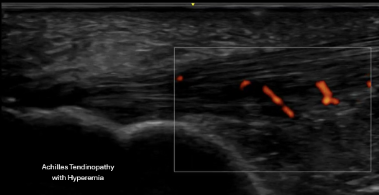

Diagnostic ultrasound evaluation of mid-portion Achilles tendinopathy with hyperemia

Achilles Pathology

• Mid-portion tendinopathy

• Insertional tendinopathy

• Partial thickness tears

• Fat pad impingement

• Achilles bursitis

• Chronic degenerative tendon changes

Ultrasound allows us to:

• Directly visualize tissue structure

• Perform dynamic evaluation during movement

• Compare side to side

• Correlate imaging with symptoms in real time

You leave knowing exactly what is involved — not just a generic diagnosis of “heel pain.”